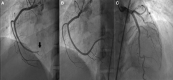

Case summary: Thirty-four-year-old woman with the unremarkable medical history presented with epigastric pain and dyspnoea. Electrocardiogram showed ST-segment elevation in the inferior limb leads. She underwent an emergency coronary angiogram, which showed a high thrombus burden in the distal right coronary artery. A subsequent echocardiogram demonstrated a 31 × 33 mm right atrial mass adhering to the inferior vena cava and abdominal computed tomography (CT) scan revealed a 113 × 85 mm necrotic mass in the left adrenal bed, with tumour thrombus extending proximally to the confluence of hepatic veins immediately inferior to the right atrium and distally to iliac vein bifurcation. Blood parameters, thrombophilia panel, vanillylmandelic acid, 5 hydroxy indole acetic acid, and homovanillic acid levels were normal. Tissue sampling confirmed the diagnosis of PHEOs. The surgical procedure was not planned due to the presence of metastatic foci on imaging, including positron emission tomography (PET)-CT. Anticoagulation with rivaroxaban and treatment with 177Lu-DOTATATE-based peptide receptor radionuclide therapy (PRRT) was initiated.